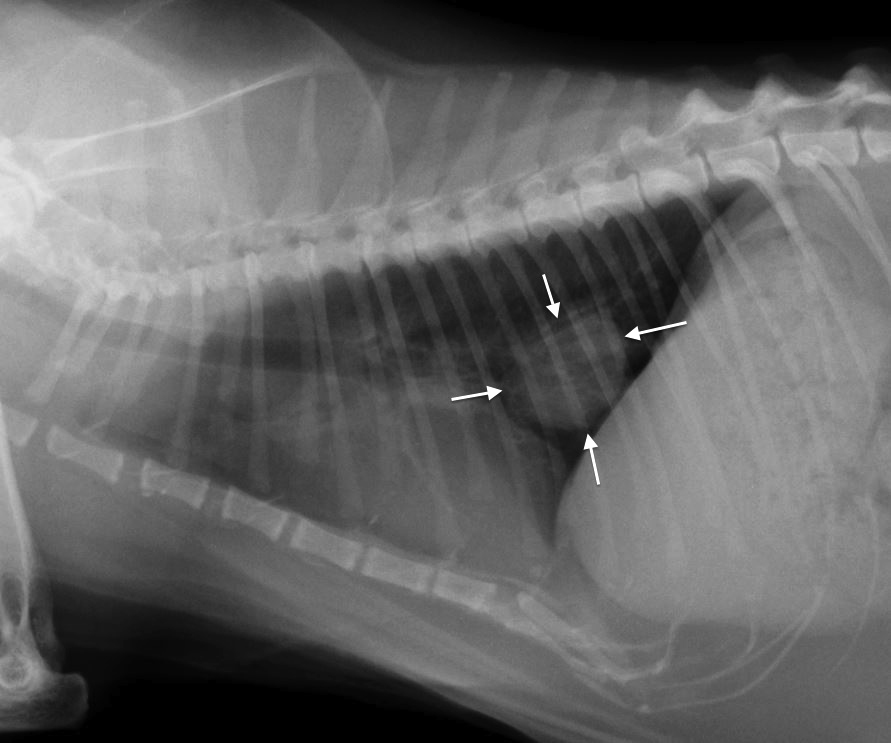

Secondhand smoke can cause lung and nasal cancer in dogs, malignant lymphoma in cats and allergy and respiratory problems in both animals, according to studies done at Tufts University's School of Veterinary Medicine in Massachusetts, Colorado State University and other schools.

The number of pets that die each year from tobacco exposure isn't available, but vets know from lab tests and office visits that inhaling smoke causes allergic reactions, inflammation and nasal and pulmonary cancers in pets, said Dr. Kerri Marshall, the chief veterinary officer for Trupanion pet insurance.

Lymphoma is one of the leading causes of feline death. The Tufts research showed that repeated exposure to smoke doubled a cat's chances of getting the cancer and living with a smoker for more than five years increased the risk fourfold. It can also cause a fatal mouth cancer.

Symptoms of cancer in animals include coughing, trouble eating or breathing, drooling, weight loss, vomiting, nasal discharge, bleeding and sneezing. Cancer kills more dogs and cats than any other disease, according to Denver-based Morris Animal Foundation, which has been funding pet cancer research since 1962.